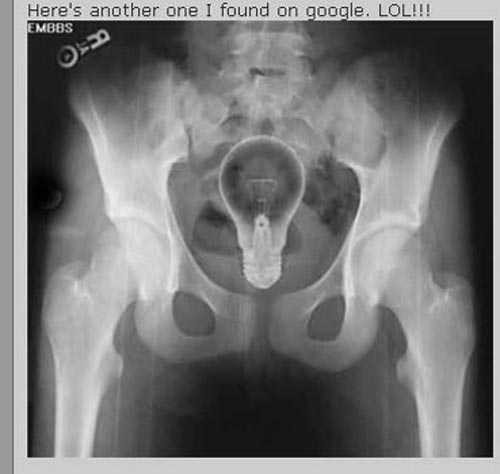

| Bóng đèn vẫn nguyên vẹn bên trong người bệnh nhân |